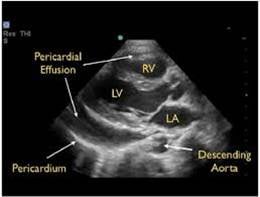

Effusion, Trauma, and Tamponade

- Pericardial effusions are common and range from benign to life threatening.

- In contrast to an effusion, epicardial fat pads are isolate to the anterior of the heart and often have increased echogenicity.

- In the setting of trauma, significant effusion may signify cardiac injury.

- The parasternal long axis view can be helpful in distinguishing between pericardial (anterior to descending thoracic aorta) and pleural (posterior to the DTA) effusions.

- Findings of tamponade on echocardiography include right ventricular diastolic collapse, right atrial systolic collapse, plethoric IVC, and increased inflow variation.19

- Pericardial tamponade is potentially lethal without intervention. Intuitively POCUS can decrease time to intervention although to date this is supported only by weak evidence.20

- Epicardial fat pads are usually isolated to the anterior heart and have internal echoes. Pericardial fluid usually collects in the dependent posterior pericardial space and can be seen surrounding the myocardium anterior to the descending aorta. A left sided pleural effusion will be located posterior to the descending aorta.

- Figure 15. Parasternal long axis showing pericardial effusion anterior to descending thoracic aorta

- Clotted blood in the pericardial space may have more hypoechoic appearance.

- Cardiac tamponade is a clinical diagnosis. Place the echocardiographic findings in the context of the patient’s clinical status.